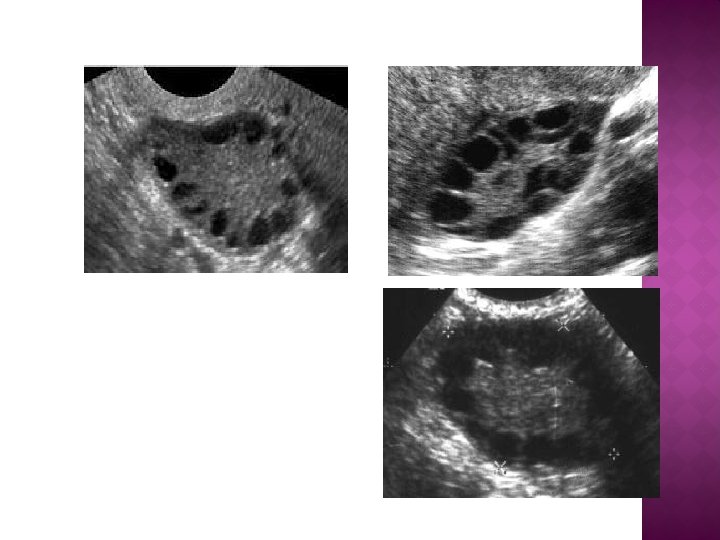

MAKING THE DIAGNOSIS � � 1. 2. 3. � � � Ovarian morphology remains the most sensitive marker for the PCOS. There are ultrasound criteria to diagnose the PCO : Increased ovary area/volume. 10 -15 microcysts less than 10 mm organized in a peripheral rosary pattern. (generally > 5 cysts) Increased echogenicity of ovarian stroma. Transvaginal sonography (TVS) is the gold standard and the most sensitive method to detect PCO. The presence of PCO does not mean that the patient has PCOS. Around 20 -25% of women have PCO detected by TVS , only about 5 -10% have PCOS.

A woman is diagnosed with polycystic ovaries (as opposed to PCOS) if she has 12 or more follicles in at least 1 ovary

Echodense “white” ovarian stroma MAKING THE DIAGNOSIS Microcysts in the periphery of the ovary Microcysts